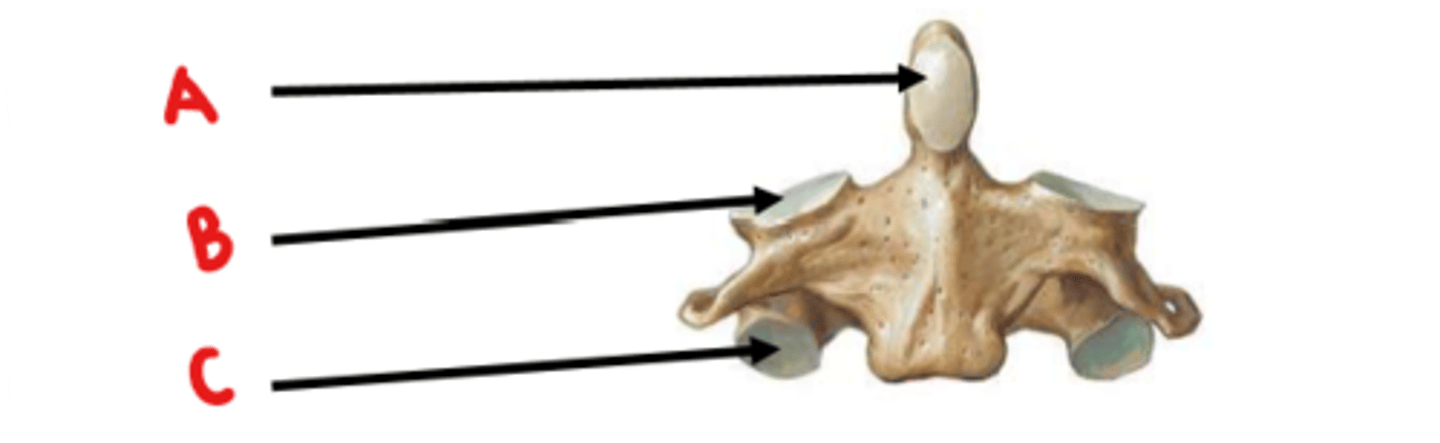

Axis (C2)

What vertebrae is this?

odontoid process (dens)

Identify A

superior articulating facet

Identify B

inferior articulating facet

Identify C